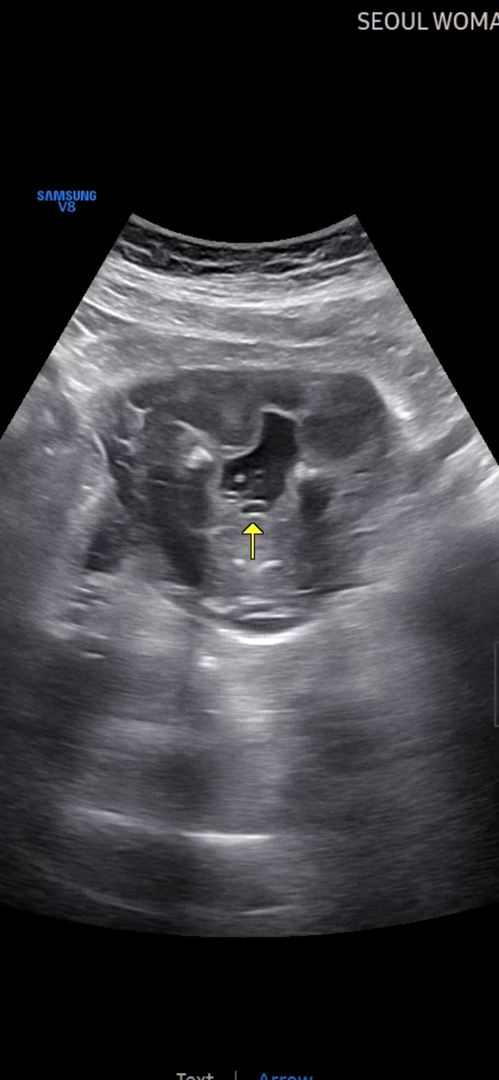

16주4일 성별

오늘 병원에가서 성별을 알아봤는데 잘 안보여서ㅠㅠ꼬추인지 탯줄인지 정확하지 않다네요🥲 정확히는 안나왔는데 아들일거 같다구 하시는데~ 한일주이주이따 성별만 다시 보러 병원오라구 하시네용😍 아들이든 딸이든 상관없지만 저만 🌶️가 안보이나요...흑ㅠ 다른 맘들은 🌶️🌶️ 확실히 보이던데ㅎㅎ 병원다녀왔지만 성별이 정확치 않아서 이거 또 궁금함을 가지며 다음병원진료를 기다려야해요😭 성별반전이 있을수 있을까융?😳😳